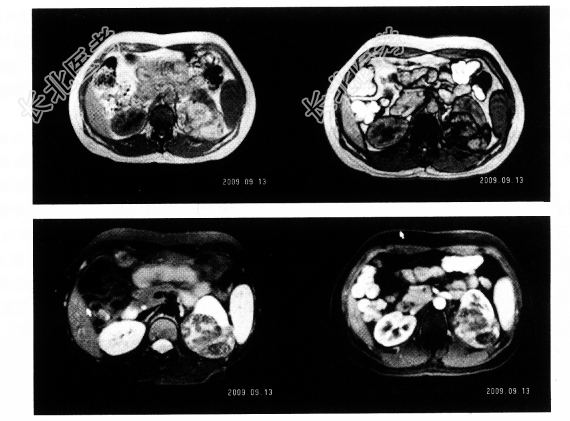

- 单项选择题3.MRI检查如下图,你诊断为

A、肾癌

B、肾盂癌

C、肾血管平滑肌脂肪瘤

D、肾脓肿

E、肾脂肪瘤

F、肾血肿